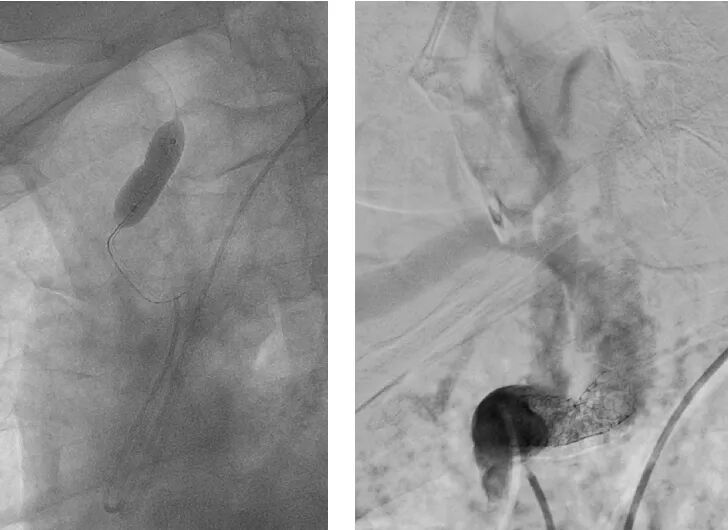

·右侧桡动脉入路造影

明确左侧锁骨下动脉起始部重度狭窄;

同时发现起始部斑块为溃疡斑块。

·球扩后植入9-30自膨颈动脉支架

桡动脉鞘怎么读【REPLAY·周三全桡日】王鹏:双侧桡动脉入路 锁骨下支架_https://www.jmylbn.com_新闻资讯_第18张